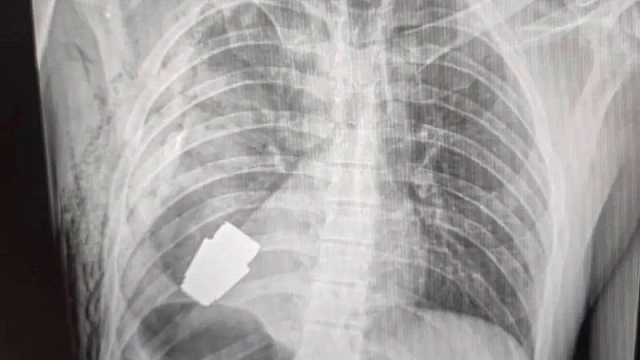

Μια μικρή χειροβομβίδα που θα μπορούσε να εκραγεί ανά πάσα στιγμή, αφαίρεσαν στρατιωτικοί γιατροί από το στήθος Ουκρανού στρατιώτη, ο οποίος αναρρώνει.

Τις φωτογραφίες που το πιστοποιούν έδωσαν στη δημοσιότητα οι Ένοπλες Δυνάμεις της Ουκρανίας.

Στην ακτινογραφία φαίνεται η χειροβομβίδα στο στήθος του στρατιώτη πολύ κοντά στην καρδιά του.

Σε άλλη φωτογραφία, ο χειρουργός -πεπειραμένος στρατιωτικός ιατρός- κρατά στα χέρια του την χειροβομβίδα, την οποία αργότερα παρέλαβαν και κατέστρεψαν ειδικοί. Κατά τη διάρκεια της επέμβασης βρίσκονταν στο χειρουργίο δύο στρατιώτες του Μηχανικού για να διασφαλίσουν ότι η επέμβαση θα είναι ασφαλής για όλους τους παριστάμενους.

Άγνωστο είναι, όπως αναφέρει το BBC, πώς βρέθηκε η χειροβομβίδα, τύπου VOG με μέγεθος τέσσερα εκατοστά, στο στήθος του άνδρα. Δεν είναι γνωστό ούτε πότε έγινε η επέμβαση.